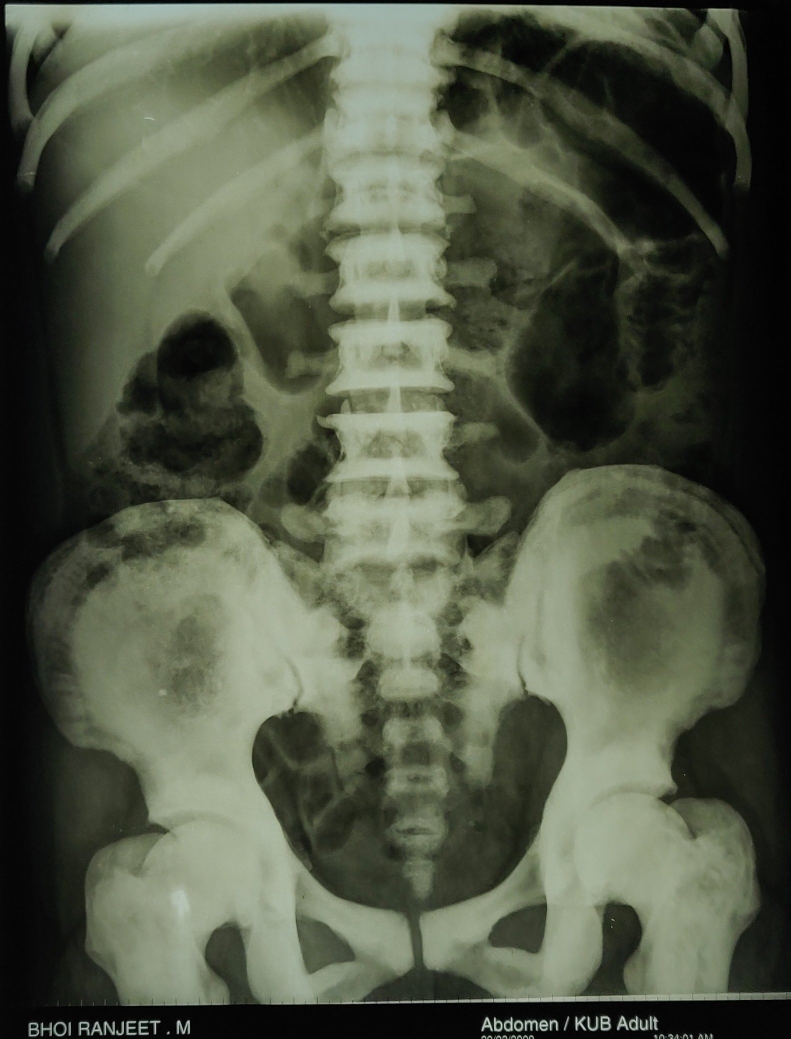

Figure 3 from Osteopetrosis (Marble Bone Disease) A Rare Disease in What Is Marble Bone Disease Therefore, the disease is often referred to colloquially as “marble bone disease.” the. Web osteopetrosis is a group of diseases that affects the growth and remodeling of bone and characterized by. Web osteopetrosis is a condition in which abnormal bone growth and high bone density can lead to a vulnerability to bone. Web osteopetrosis, or marble bone disease, is a. What Is Marble Bone Disease.